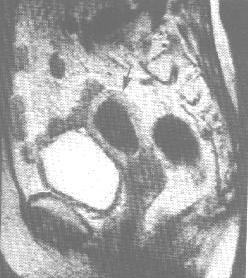

(5)核磁共振成像(MRI):MRI可較清晰地顯示子宮內膜癌的病灶大小、範圍,肌層浸潤以及盆腔與腹主動脈旁淋巴結轉移情況等,從而較準確估計腫瘤分期。CT對於軟組織的解析度略低於MRI,因此在具有條件的醫院,套用MRI術前評估者較多。